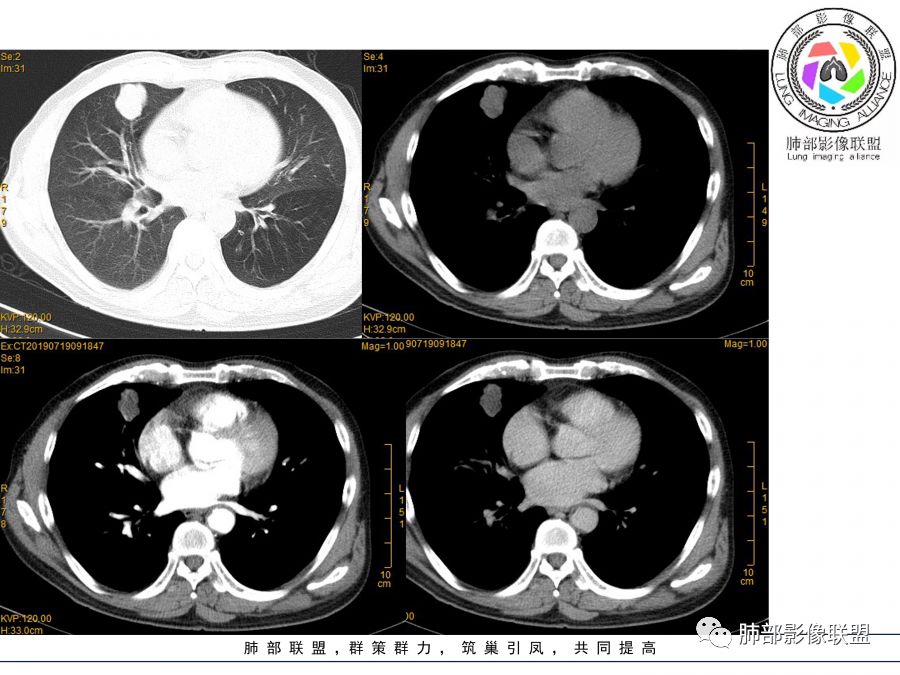

晨读病例  患者老年男性,因腰腹部疼痛3周,排尿困难1周入院。查尿常规及C反应蛋白提示泌尿系感染。肿瘤标志物NSE、细胞角蛋白19片断稍升高。胸部CT:右肺中叶内侧段类圆形肿块影,浅分叶,部分层面见深分叶,胸膜牵拉及支气管截断征象,边界清,密度低,无强化,且垮叶裂。综合考虑恶性病变,类癌及小细胞可能性大,鉴别囊肿等良性病变肺囊肿。

目测这里还是有强化,其余地方强化幅度不是很明显

浅分叶

边缘膨隆

常规会考虑恶性

1.右肺中叶孤立不规则块影,浅分叶,未见液化或钙化,未见毛刺,未见脐凹,未见明显胸膜牵拉。

2.近肺门侧隐约见支气管截止。

3.外侧可见血管进入,病灶局部轻度强化。

上述均不符合光滑类圆形的支气管肺囊肿,也不符合典型的类癌,切不可先入为主。也不符合转移瘤。

4.肺门纵隔未见增大淋巴结。如此体量的肺块,没有增大淋巴结,不符合小细胞肺癌的生物学行为。

5.未见卫星灶,未见支气管增厚,结核也缺少支持点。

综上,应当鉴别的主要为肺鳞癌及结核灶

中低分化鳞癌